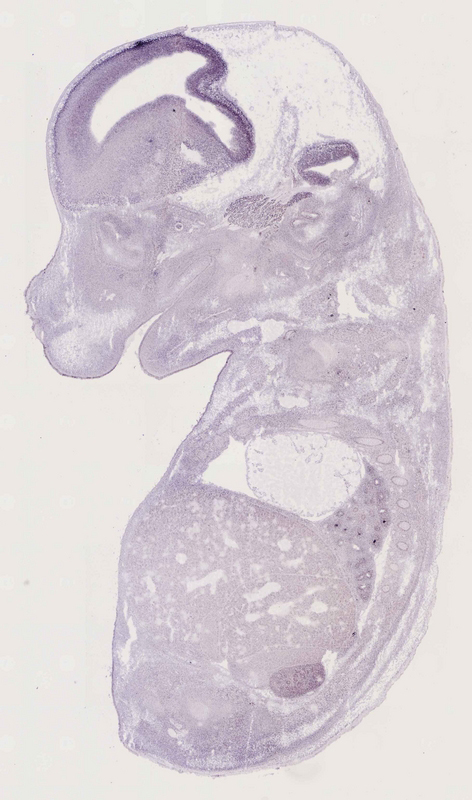

Specimen

euxassay_013785_01:

embryonic day 14.5

euxassay_013785_02: